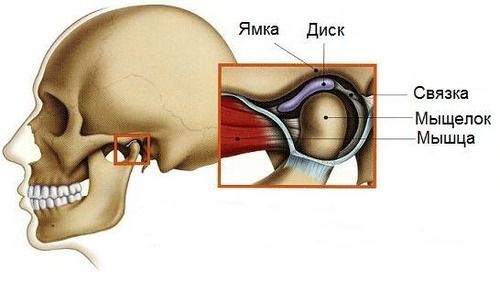

- патологии височно-нижнечелюстных суставов (ВНЧС), например артроз (ВНЧС соединяют нижнюю челюсть с основанием черепа);

Артроз ВНЧС

1. Дисфункция ВНЧС. Патология проявляется:

- хрустом, щелчками и болями в ВНЧС;

- болями и шумом в области ушей, их заложенностью и снижением слуха;

- болями при жевании, а также ограниченным открыванием рта.

Для артрогенных расстройств ВНЧС, т. е. связанных с разрушением сустава, характерны:

- шум в ВНЧС;

- боль в области сустава при пальпации (прощупывании);

- неравномерные движения нижней челюсти.

Кроме того, при движении челюсти может смещаться хрящевой диск, который защищает сустав от разрушения. Он может возвращаться на правильное место к головке мыщелкового отростка (смещение с вправлением) или оставаться смещённым (смещение без вправления). Иногда изменяются формы костной ткани в области суставного отростка (части ВНЧС). В таких случаях ВНЧС является основным источником боли, а жевание её усиливает [5].

Строение височно-нижнечелюстного сустава